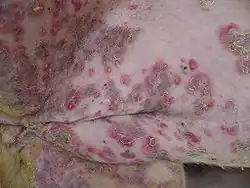

Animals affected

Pemphigus foliaceus has been recognized in pet dogs, cats, and horses, and is the most common autoimmune skin disease diagnosed in veterinary medicine. PF in animals produces clusters of small vesicles that quickly evolve into pustules. Pustules may rupture, forming erosions or become crusted. Left untreated, PF in animals is life-threatening, leading to not only loss of condition, but also secondary infection.

PV is a very rare disorder described in pet dogs and cats. Paraneoplastic pemphigus has been identified in pet dogs.